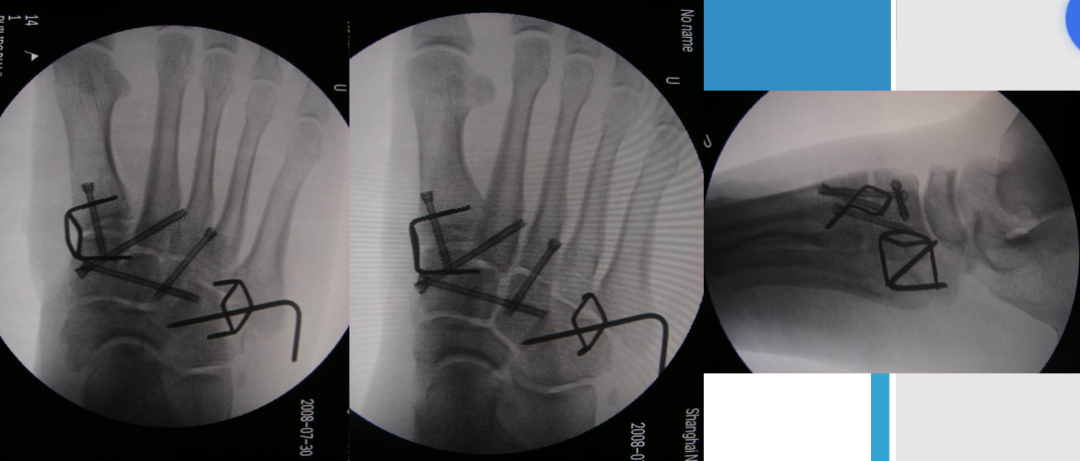

根据三柱理论1、首先复位内侧柱并临时固定 2、再复位固定中间柱3、如外侧柱移位可能需双切口

手术从第一跖骨和内侧楔骨开始。首先直视下复位该关节,评价楔骨之间的稳定性,关节囊通常撕裂,但仍然需要掀开以充分显露关节,清除关节内的软组织和软骨碎片。

内侧柱稳定后,开始处理第二跖骨和中间楔骨。点式复位钳由第二跖骨基底部外侧远端斜向内侧楔骨内侧面的近端夹持,注意避免第二跖骨向下移位,发生复位不良。

若楔间关节仍不稳,可使用楔骨间螺钉;固定内侧两跖骨后,通常第三跖骨已经足够稳定,若仍未复位,可以参考第一跖骨固定方法固定。通过第二切口固定第4、5跖骨。可以使用克氏针固定。

Lisfranc损伤骨折复位标准:1、C形臂透视显示正、侧、斜位均为正常解剖复位2、如复位后第1、2跖骨基底间隙和内、中楔骨间隙<2mm,跖跗骨轴线<15°为近解剖复位,可以接受,超过这个范围的移位则无法接受3、复位好后,沿第一跖骨轴线向内侧楔骨逆行拧入一枚4.0mm皮质骨螺钉。螺钉由关节远侧1.5-2.0cm处进入,平行于足底或略向跖侧。

4、从内侧楔骨向第二跖骨置入一枚螺钉,重建韧带。螺钉自内侧楔骨近端的背侧置入,指向第二跖骨背侧皮质的下方,螺钉应通过4层皮质,确保对第二跖骨的双皮质固定

术后管理石膏固定4~6周;如果固定稳定,术后两周可开始功能锻炼,4~6周部分负重,六周后完全负重;术后6~8周可拔去克氏针,术后3~4月可取出螺钉。有些人主张若无症状出现,可无限期地留置螺钉于体内

单纯克氏针、螺钉固定不适用于粉碎性骨折,特别是合并短缩的骨折,后期易导致畸形愈合。克氏针外固定架联合固定可对内侧柱进行支撑复位;对于内侧柱粉碎骨折患者,微型外固定架有一定的优势。